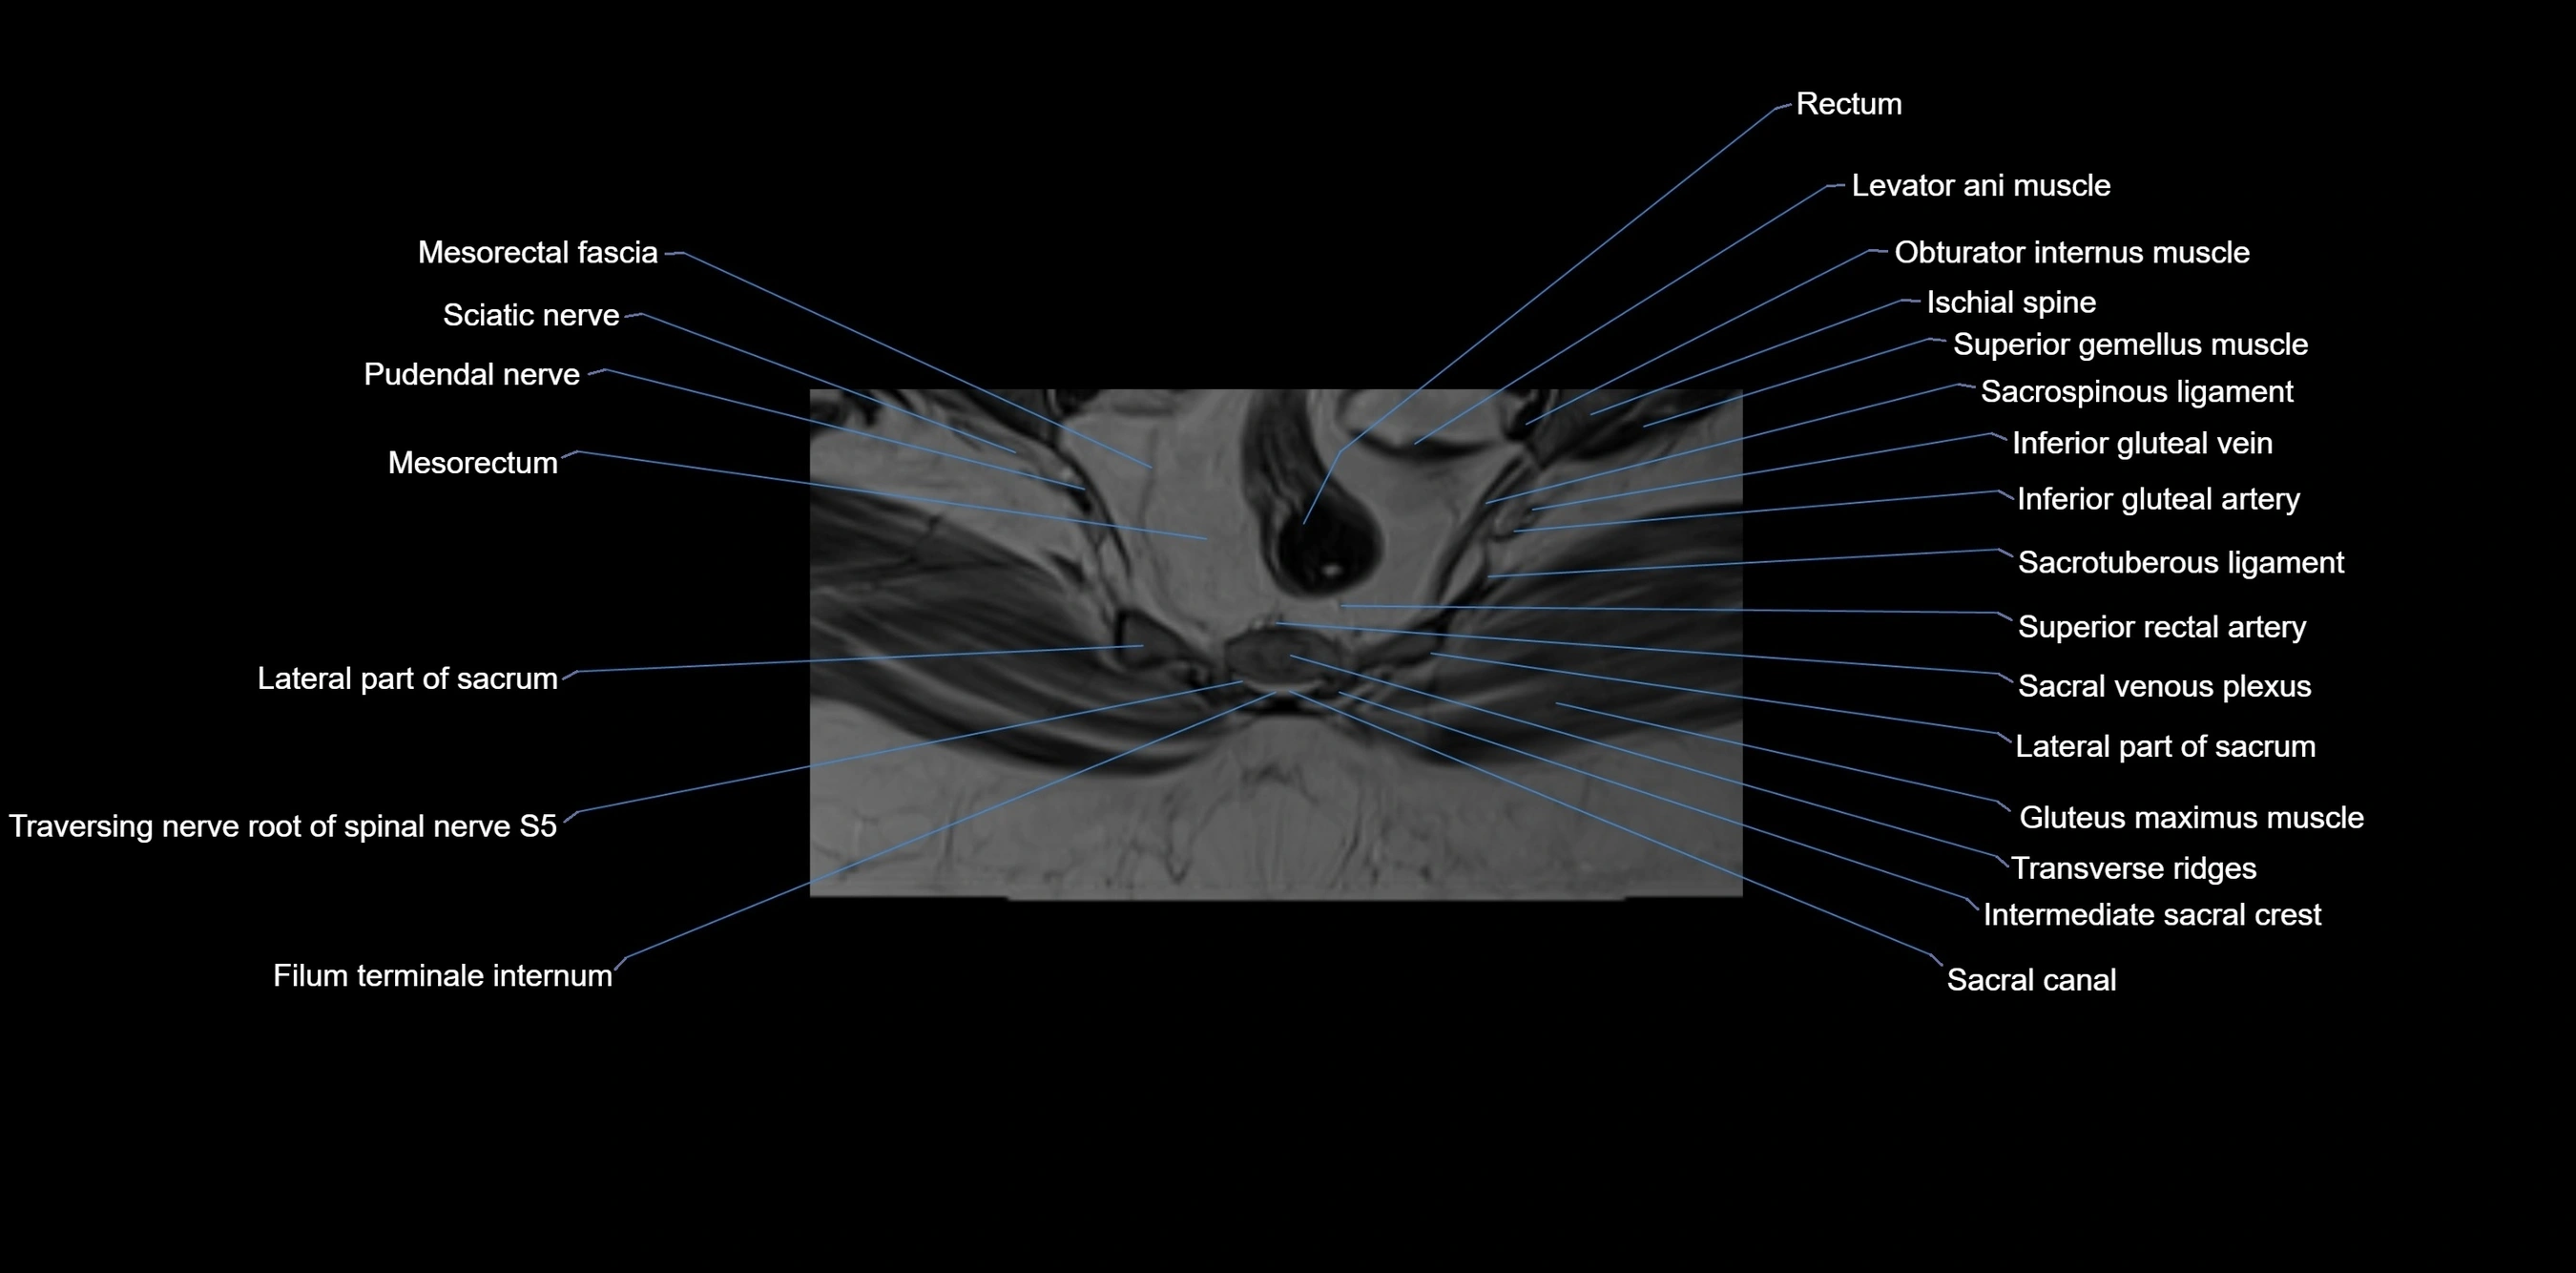

MRI image

image